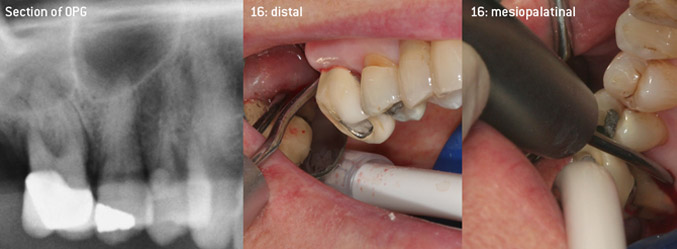

As initiators of the development of the new diamond-coated 3AP air scaler tip, the two dentists recognized the need for improvement of the handling restrictions of the commercially available diamond-coated tips, especially during furcation treatment and when working in tight intraosseous pockets. This should be possible for both non-surgical (Figure 2) and surgical (Figure 3) procedures.

Open debridement of the furcations on teeth 16 and 17

Fig. 3: Open debridement of the furcations on teeth 16 and 17 in case of advanced attachment loss

The aim was to develop a universally applicable tip in order to avoid time-consuming tip changes. In addition, it should be easier to use the new working tips in tight intraosseous pockets from distal and at the distal furcation entrance of maxillary molars, allowing more effective use of instruments as a result. This was achieved by employing an instrument curve with a larger diameter (Figure 1), which is highly advantageous for closed debridement on teeth with advanced attachment loss and involvement of furcation in particular (Figure 4).